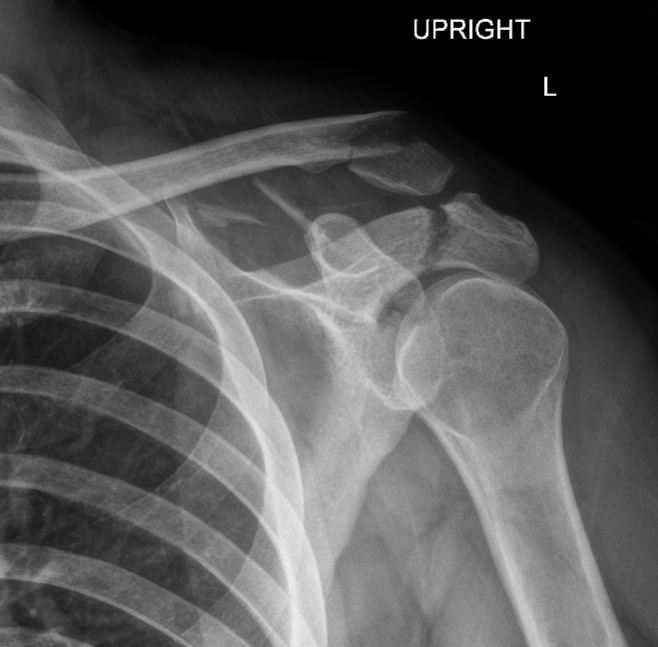

Glenoid fracture + lateral clavicle fracture + acromial fracture